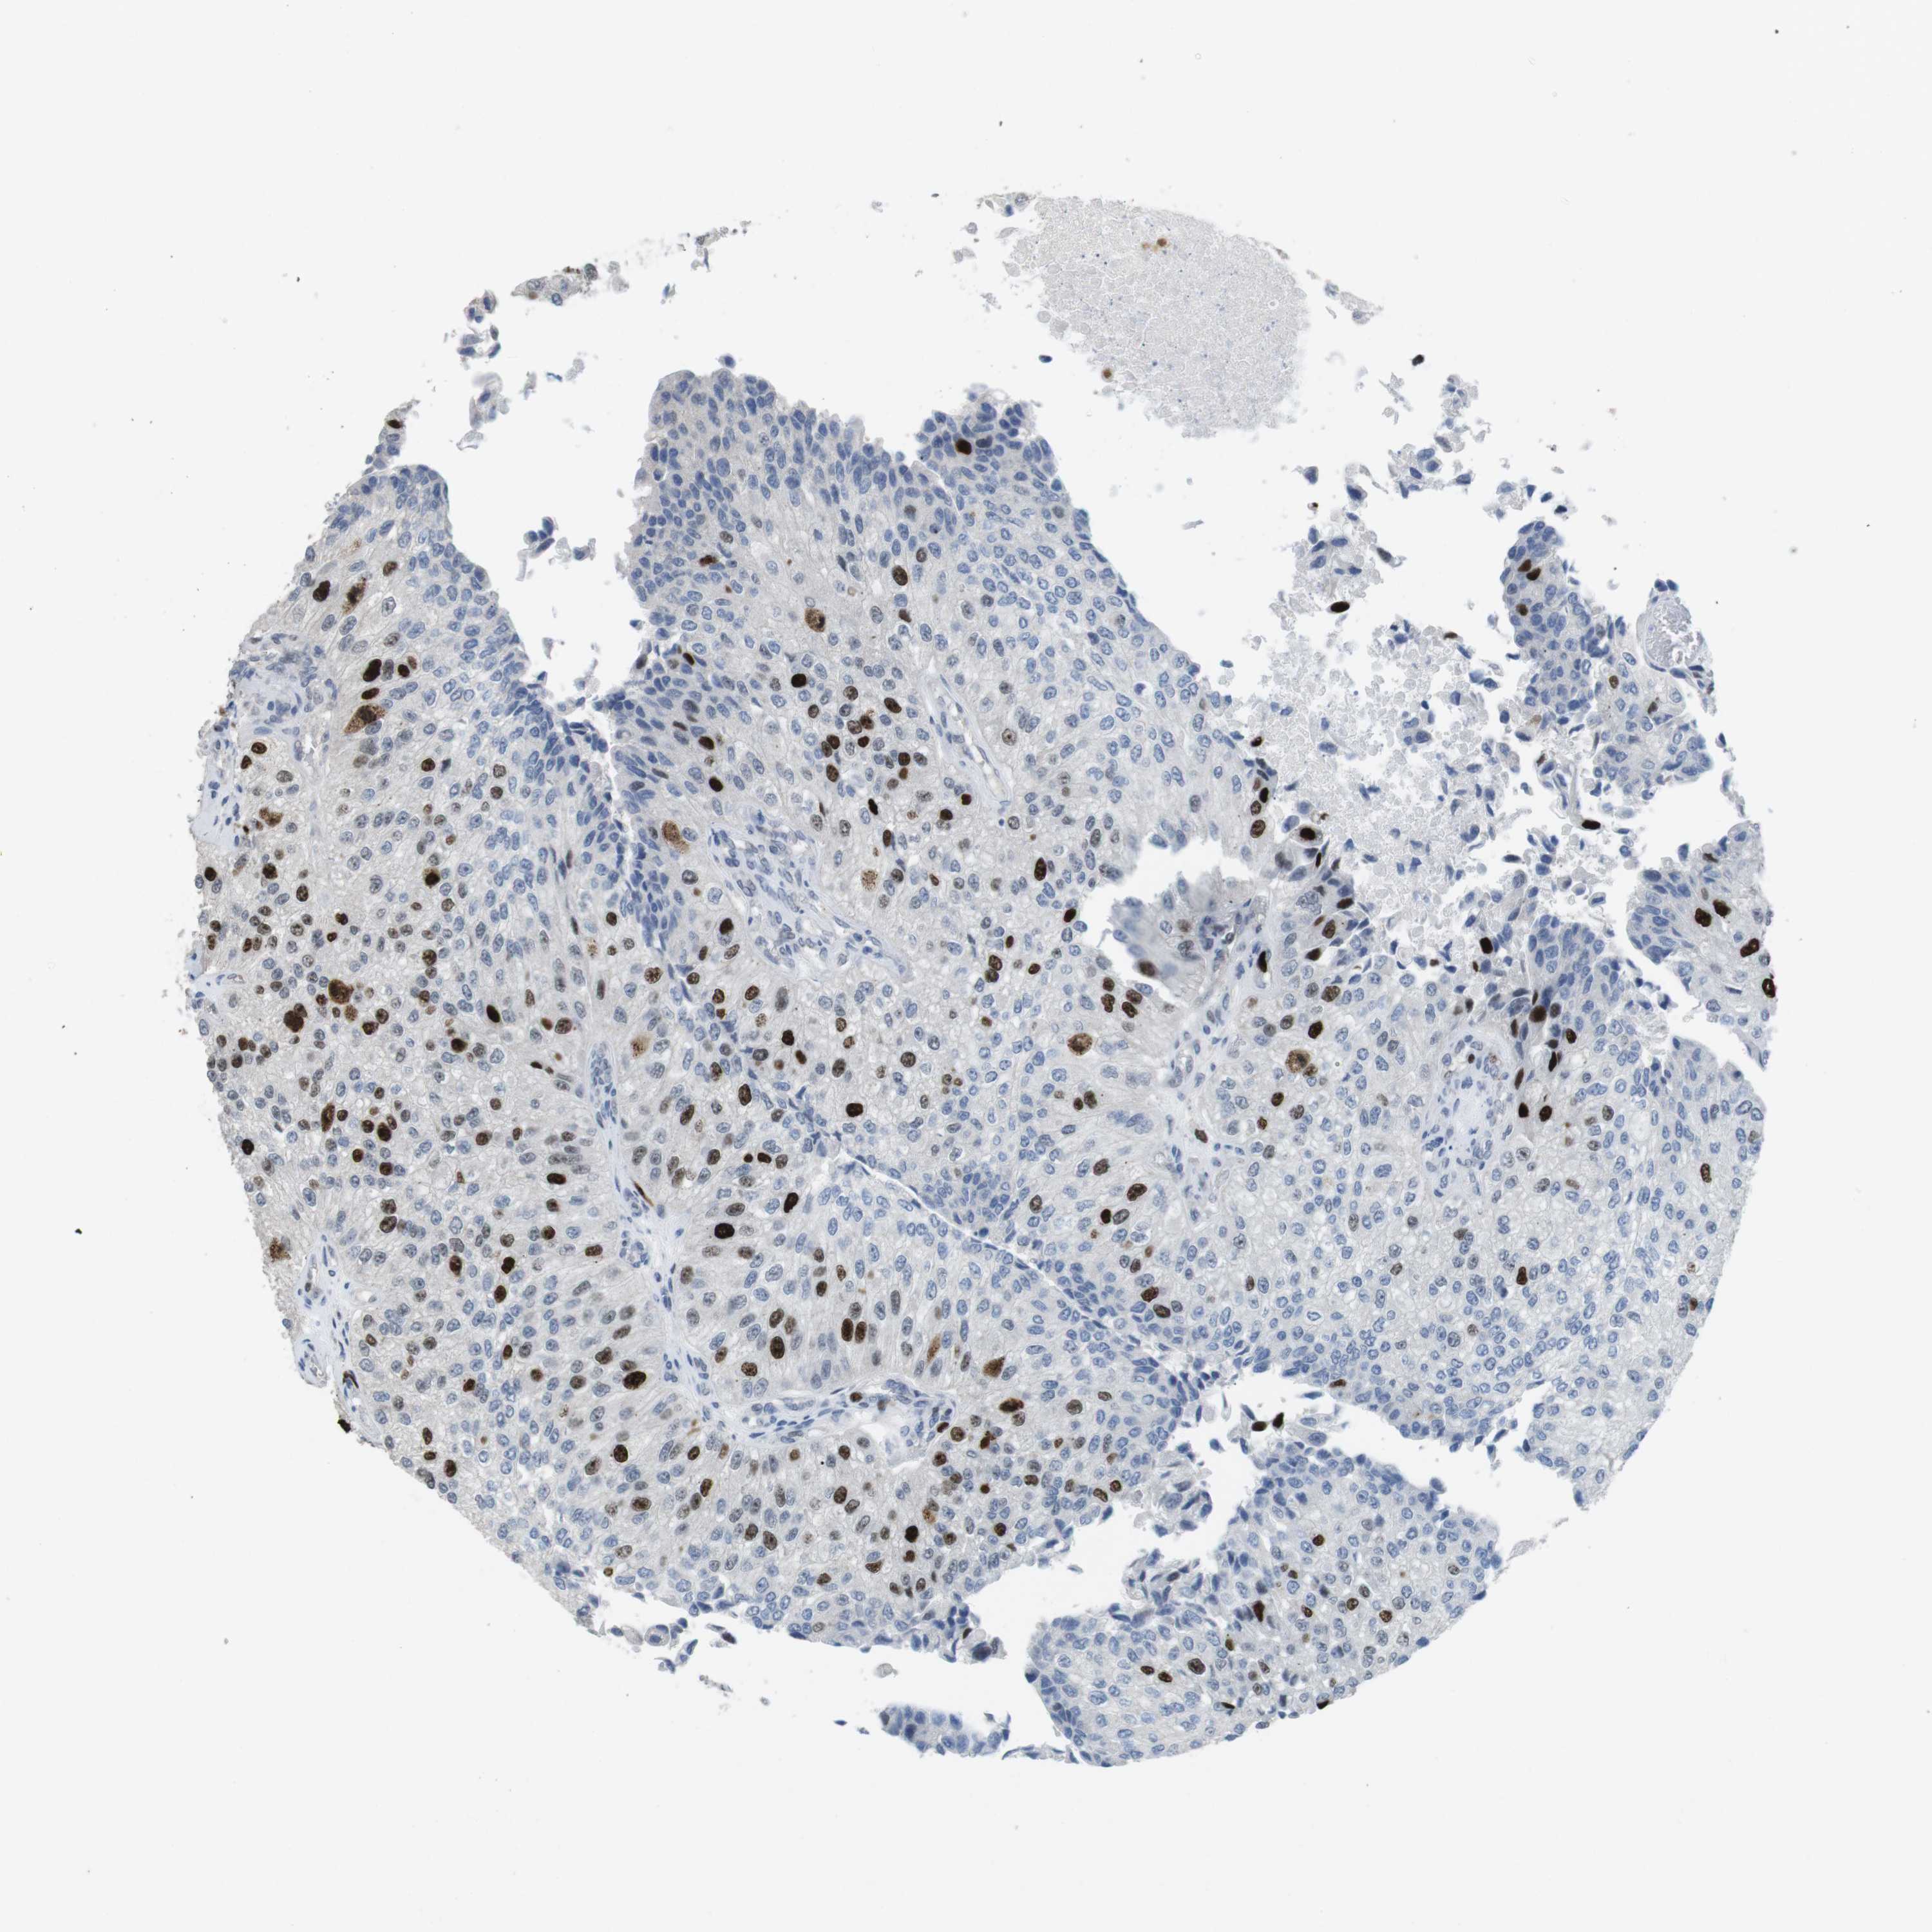

UROTHELIAL CANCER - Protein expressioni

A mouse-over function shows sample information and annotation data. Click on an image to view it in a full screen mode. Samples can be filtered based on level of antibody staining by selecting one or several of the following categories: high, medium, low and not detected. The assay and annotation is described here.

Note that samples used for immunohistochemistry by the Human Protein Atlas do not correspond to samples in the TCGA dataset.

Antibody stainingi

Antibody staining in the annotated cell types in the current human tissue is reported as not detected, low, medium, or high, based on conventional immunohistochemistry profiling in selected tissues. This score is based on the combination of the staining intensity and fraction of stained cells.

Each image is clickable and will lead to virtual microscopy that enables deeper exploration of all samples and also displays staining intensity scores, fraction scores and subcellular localization as well as patient and tissue information for each sample.

Antibody HPA041270

Antibody CAB015460

Staining

High

Medium

Low

Not detected

Intensity

Strong

Moderate

Weak

Negative

Quantity

>75%

75%-25%

<25%

None

Location

Nuclear

Cytoplasmic/membranous

Cytoplasmic/membranous,nuclear

Urothelial carcinoma, High grade